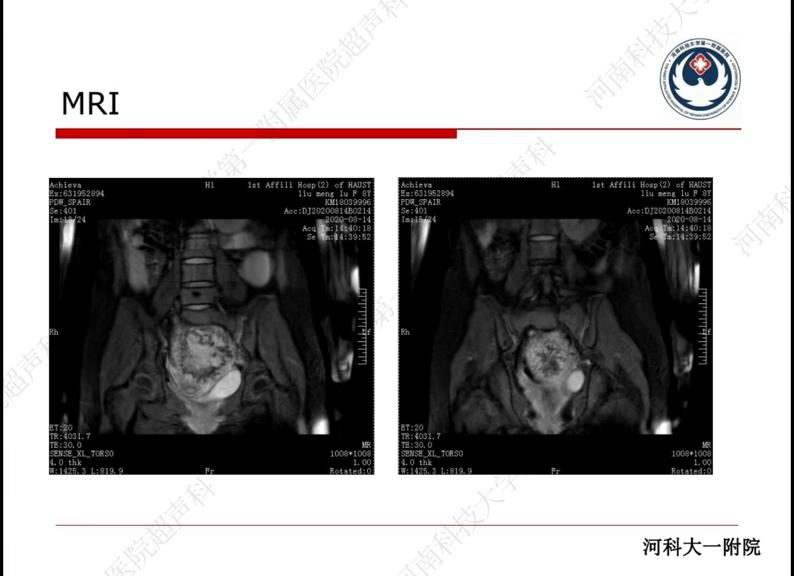

主诉:患者间断下腹部疼痛已有1年之久,最近3天疼痛加重。现病史:患者自2020年6月至7月间曾出现阴道出血,持续2个月,随后在当地医院接受药物治疗,但出血并未停止,具体情况不详。患者自述近1年多以来不时感到下腹疼痛,曾在当地医院被诊断为胃部不适,给予对症药物治疗,但疼痛无法缓解。最近一周,下腹疼痛再次发作,药物治疗后症状有所缓解,但仍感精神差、食欲不佳,睡眠正常,大小便正常,体力下降。经检查,发现患者患有盆腔囊实性包块,具体情况如下:左侧附件区多房囊性包块,大小约为15*10cm;右侧附件区一巨大囊性结构,大小约为10*15cm,边界不清,与膀胱、子宫壁分界不清,考虑为肿瘤性病变;L5椎体周围异常信号,建议结合临床及后续检查结果。手术中诊断:患者患有盆腔巨大肿瘤、双卵巢肿瘤、肠粘连和贫血等多种疾病。手术经过:术中发现患者盆腔内有一10*15cm的巨大肿瘤,呈囊实性,表面暗褐色,表面覆盖部分大网膜和肠管,粘连组织见有陈旧性出血迹象。同时发现患者的双卵巢各有一个10*10cm的肿瘤,呈多房性,内含黄色液体和血性液体。左侧卵巢肿瘤似乎与盆腔巨大肿瘤相连。手术中剥除了肿瘤,但在剥离肿瘤底部时仍有明显渗血,考虑患者术中出血过多,因此在盆腔底部放置了止血纱布条进行压迫止血。手术中发现患者的肠管和部分大网膜粘连,粘连组织有陈旧性出血迹象。在分离粘连组织时,发现组织脆,特别容易出血,因此在分离粘连后发现巨大包块位于子宫和肠管之间,并与子宫后壁和肠管紧密粘连。双卵巢各有一个6*7cm的肿瘤,通过分离粘连后成功切除。手术中患者特别容易出血,心率持续波动在150-195次/分,血压需要间断使用升压药物维持。术中出血过多,约3000ml。手术结束后,患者被送回重症医学外科,血压为100/60mmHg,呼吸为20次/分,脉搏为180次/分。(盆腔)结合免疫组化结果,证实患者患有绒癌,即妊娠性绒癌。绒癌是一种高度恶性的滋养细胞肿瘤,其特点是无绒毛、无血管无间质的“三无产品”。绝大多数绒癌继发于正常或不正常的妊娠之后,主要发生在育龄妇女身上,是由妊娠滋养细胞恶变所致。男性*丸睾**和女性卵巢也常同时出现绒癌,此外还可能与其他生殖细胞肿瘤并存(如内胚窦瘤、未成熟的暗胎细胞等)。在生殖器以外的原发部位,纵隔或异位绒癌指的是原发于子宫以外的输卵管或卵巢绒毛膜癌,而不是由宫绒癌转移形成的。这种情况非常罕见。

CT/MRI可以发现早期转移灶。